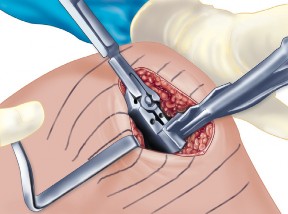

الشق الجراحي:

يُستخدم شق طولي في الجانب الإنسي (الداخلي) من الركبة. يجب أن يكون الشق كبيرًا بما يكفي لتوفير رؤية جيدة للمفصل الرضفي الفخذي وإمكانية التحويل إلى TKA.

- فتح المفصل (Arthrotomy): يكون الفتح خطيًا وموازياً لألياف الوتر الرضفي، ويمتد إلى عظم الظنبوب وإلى الجزء السفلي من الرضفة.

- تحرير الأنسجة الرخوة: يتم قطع الغضروف الهلالي لتحرير الأنسجة الرخوة من عظم الظنبوب، ويتم تطوير سديلة تحت السمحاق في نمط دائري حول الظنبوب. يُمدد هذا التحرير خلفيًا لضمان توازن الأربطة.